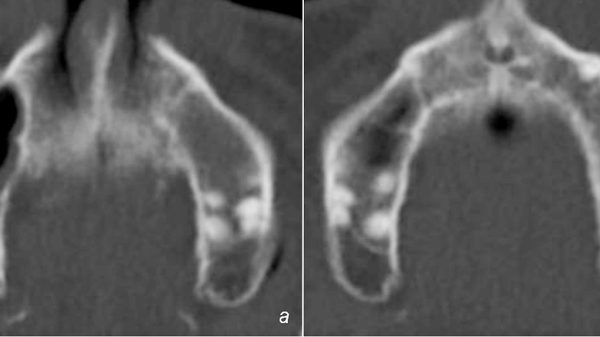

Differentialdiagnostisch sind die einzelnen Formen nicht immer leicht zu unterscheiden und auch die Differentialdiagnose zum Parodontalabszess fällt nicht immer leicht. Sowohl der Vitalitätsprobe als auch der radiologischen Diagnostik kommt hier eine besondere Bedeutung zu . Auch bei den Endo-Paro- Läsionen ist eine akute Exacerbation mit der Ausbildung von Abszessen möglich. Deren Akutbehandlung entspricht im Wesentlichen dem bei den Parodontalabszessen geschilderten Procedere. Darüber hinaus kann bei primär endodontalen Läsionen mit devitalen Zähnen eine Trepanation derselben erforderlich sein. Die Folgetherapie ist davon abhängig, ob eine primär endodontale oder eine primär parodontale Läsion vorliegt.